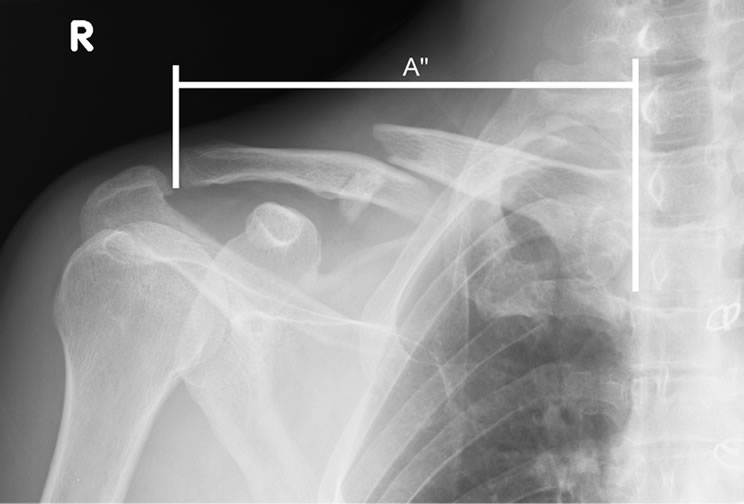

Clavicle Fracture Future Problems . Acute fractures of the proximal third of the clavicle often stem from high energy trauma and are associated with severe internal. The clavicle (collarbone) is one of the most fractured bones in the body. Our study revealed that patients with clavicle fractures treated with plate fixation had statistically significant good functional. Midshaft clavicle fractures are common traumatic injuries caused by a direct impact to the shoulder girdle and is most commonly seen in young, active adults. Despite conflicting evidence, most studies indicate that superior clinical results. Symptoms of a broken collarbone include severe pain and swelling at the site of the fracture and with visible deformity in some cases. A fall or a blow to your shoulder can fracture your collarbone (clavicle). Most collarbone fractures heal on their own with.

from orthopedicreviews.openmedicalpublishing.org

Return to Full Function in Patient with Nonoperative Management of a Comminuted, Displaced